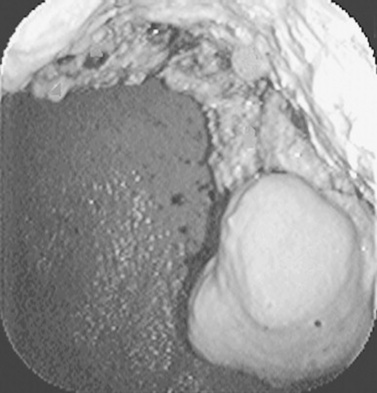

Ultrasound evaluation of horses with abdominal pain (colic) provides a rapid method to identify abnormalities within the gastrointestinal tract. Distention of the small intestine to a diameter greater than 5 cm has been strongly associated with strangulating or obstructing lesions19 (Fig. 32-11). In foals with intussusception, the small intestine appears enlarged and there is generally distended small intestine orad to the lesion; however, at the site of the intussusception there is a normal-appearing small intestinal wall (intussuscipiens) surrounded by a larger structure that appears to surround the inner small intestinal wall (called the intussusceptum)19 (Fig. 32-12). Large colon torsion occurs when the large colon rotates 360 degrees or more around the root of the mesentery to cause occlusion of venous drainage while maintaining arterial flow. This causes the wall to become thick and edematous. If ultrasound is performed in the cranioventral abdomen, just caudal to the xiphoid process, then a colon wall size greater than 9 mm is 100% specific for a large colon torsion21 (Fig. 32-13). A large colon displacement would have minimal to no vascular compromise, so it would be an ultrasound diagnosis based on exclusion. Chronic displacements did have a mild amount of edema in the colon wall, causing the size to be approximately 7 mm thick but never greater than 9 mm in the one study described.21 The colon and small intestinal wall will also become thick with inflammation. Small intestinal wall thickness greater than 4 mm is indicative of inflammation.19 The right dorsal colon can be imaged in the right tenth to twelfth intercostal space around the region of the costochondral junction, and a focal wall thickness of 9 to 12 mm has been identified with right dorsal colitis.23

image

Fig. 32-12 Transabdominal ultrasound image of an adult standardbred mare. The image shows an inner intestinal structure surrounded by a second intestinal structure consistent with an intussusception. At surgery this was confirmed as an ileocecal intussusception.

Courtesy of Cornell University.